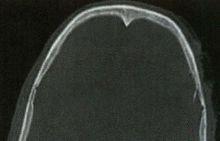

頂結節B

左側額、頂骨骨折;顱內積氣;頭皮血腫

注A、B:頭部CT軸位片。

【影像徵象】左側額、頂骨骨皮質斷裂,左側頂骨內板向內凹陷,顱內見點狀氣體影。

【影像擬診】左側額、頂骨骨折;顱內積氣;頭皮血腫。

【最終診斷】左側額、頂骨骨折;顱內積氣;頭皮血腫。

【述評】腦顱骨骨折以頂骨骨折多見,可以是開放型和閉合型。本例為開放型,顱內如果見到氣體即提示為開放型,有時顱內進氣很少,閱片是應仔細觀察。顱骨骨折可以是線樣、凹陷性、粉碎性和顱縫分離等類型。顱骨骨折通常在遭受到直接暴力下發生,由於頭皮軟組織的特點,局部通常會形成頭皮血腫,所以閱片時應重點在有頭皮血腫的位置仔細觀察是否有骨折,特別是細小的骨折,減少遺漏病變。線性骨折應要注意同顱縫相區別,線性骨折一般清晰、銳利,骨縫一般不那么銳利,雙側對稱。如果顱縫寬度成人>1.5mm、兒童>2mm或雙側相差>1mm,應視為顱縫分離。顱骨骨折時,顱內有時可見到顱內板下的血腫,本例就可見硬膜外血腫或硬膜下血腫(未展示),一般情況在骨折局部硬膜外血腫居多,對沖部位硬膜下血腫居多。發生於顱底的骨折,有時需薄層掃描方可顯示,需要仔細觀察,因為臨床意義重大。